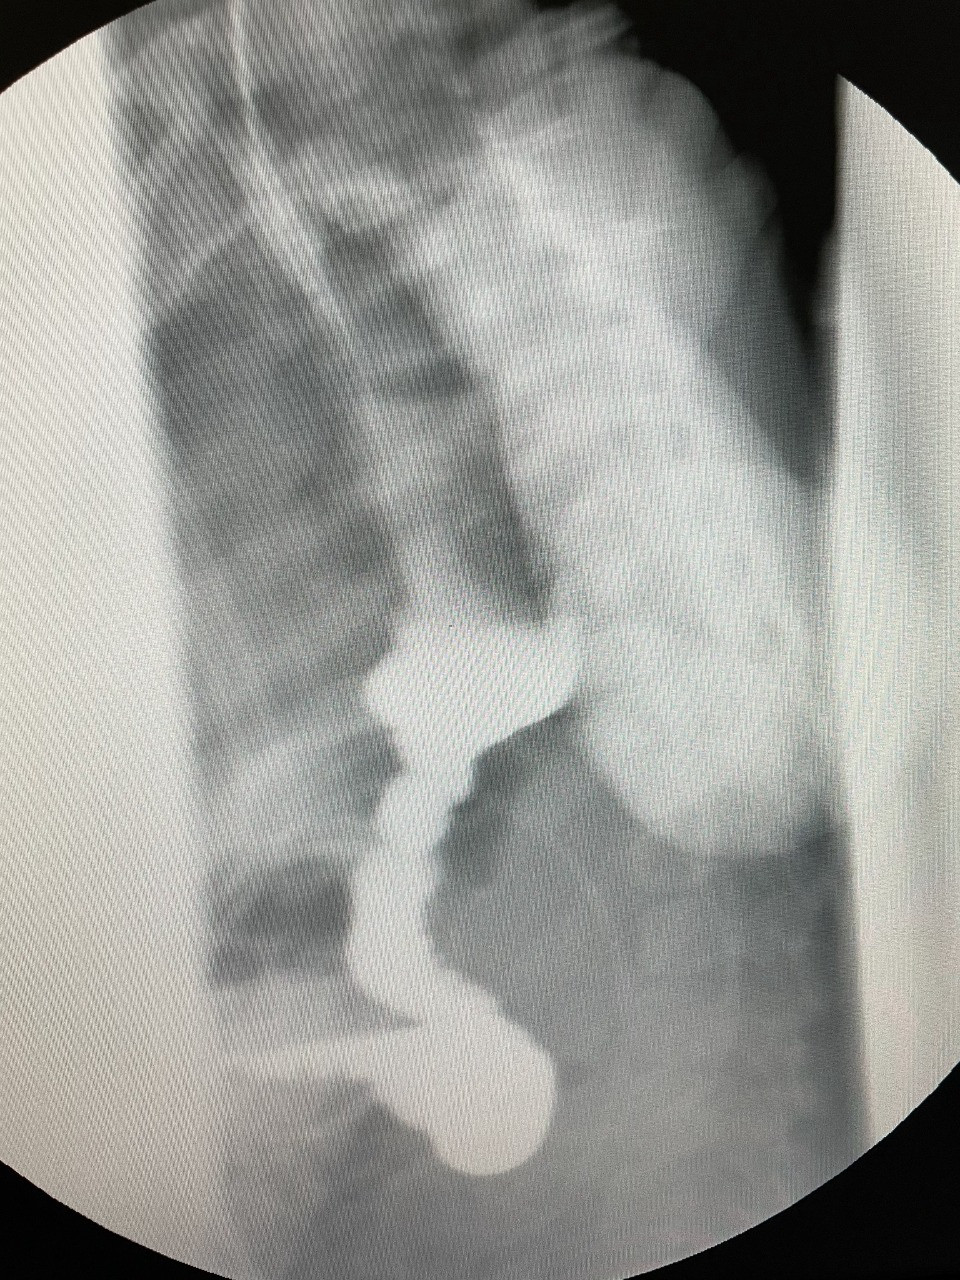

Lent.az-ın məlumatına görə, qida borusunun fistulsuz atreziyası (qida borusunun böyük qisminin anadangəlmə olmaması) ilə doğulmuş uşağa yenidoğulan dövrdə uşaq cərrahı Gündüz Ağayev tərəfindən Ezafaqo və Qastrostomiya əməliyyatı icra olunub.

1 il müddətində mədəyə qoyulmuş rezin boru ilə qidalanan uşaq 1 yaşında növbəti cərrahi əməliyyat üçün "Leyla Medical Center"ə gətirilib və xəstəyə yenə Rusiya Federasiyasının tibb elmləri doktoru Gündüz Ağayev tərəfindən, bu qüsur zamanı Azərbaycanda ilk dəfə olaraq qida borusunun əvəzlənməsi əməliyyatı icra edilib. Əməliyyatda mədə arxa divararalığından, ürəyin, aortanın və traxeyanın arxasından boyuna çıxarılaraq, qida borusunun ucu ilə birləşdirilib.